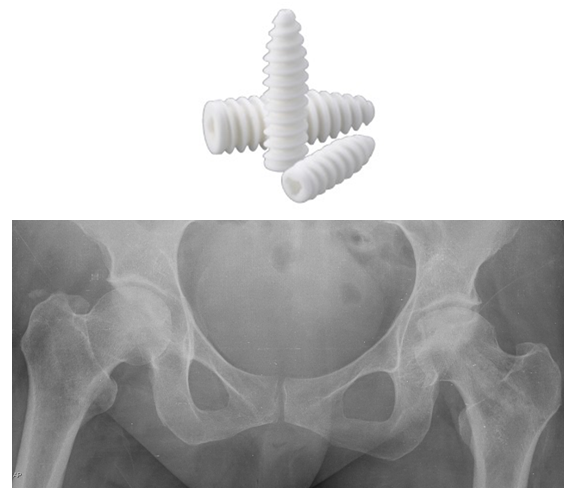

We present a case of early osteonecrosis of the hip (Ficat stage II) treated by core decompression and followed up for close to 12 months. To prevent the mechanical failure of the subchondral bone and articular collapse, we used cancellous allograft soaked in patients own blood impacted up the core decompressing channel and utilized an absorbable Interference Screw to hold the graft in place. Theory being to strengthen structural mechanics of the femoral head, provide structural support of articular cartilage bring in osteoblasts and cell mediators whilst decompressing or coring out the devitalized bone and encourage new bone formation.

This case report attempted to integrate several treatment principles in avascular necrosis. We used interference screw loaded with DBM to treat the early-stage of femoral head osteonecrosis. The goal is to tip the balance of the creeping substitution process by accelerating bone healing while providing enough structural support to the articular cartilage. The rationale for the procedure is based on the following hypotheses: